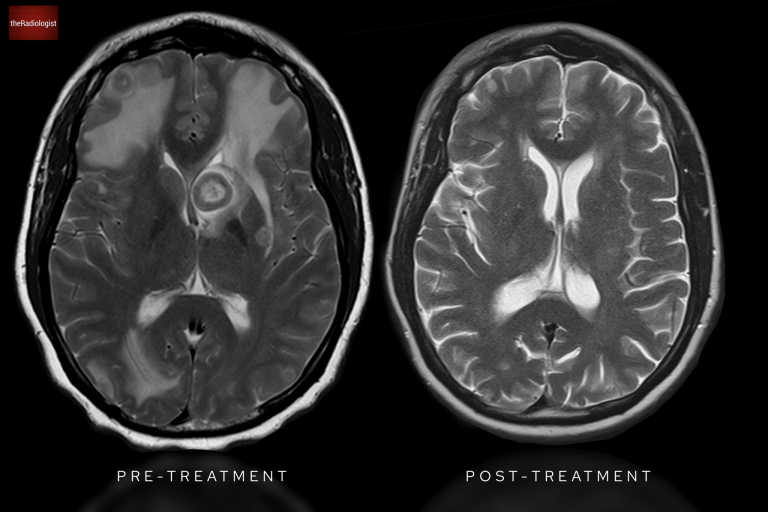

To better understand, let’s compare this with cytotoxic oedema, as seen in a stroke. Have a look at the picture below.

• In vasogenic oedema, as in our case, only the white matter is affected.

• In cytotoxic oedema, like in this case of ischaemic stroke, both the grey and white matter are involved, reflecting cellular damage.

Compare the appearance of a stroke and cytotoxic oedema involving both grey and white matter (left) with space occupying lesions on the right involving white matter only and causing vasogenic oedema with so called ‘finger like projections’ (right)

The imaging findings, combined with clinical context, revealed these lesions were due to metastatic breast cancer. Post-chemotherapy imaging shows a remarkable improvement, with the lesions no longer visible.

Post chemotherapy MRI shows resolution of all brain metastases.